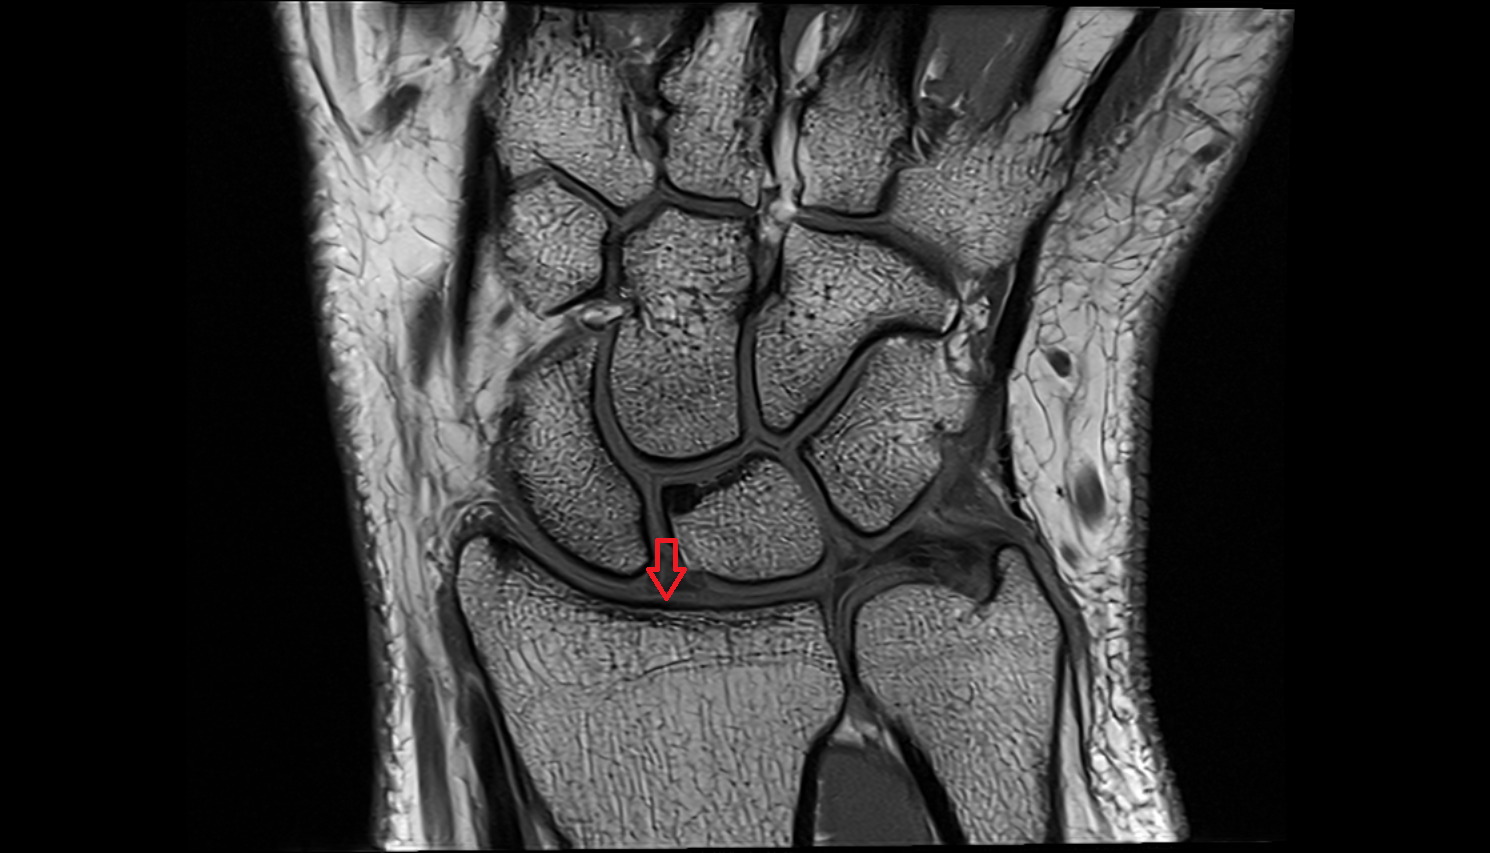

- Transverse tarsal joint

- Tarsometatarsal joints